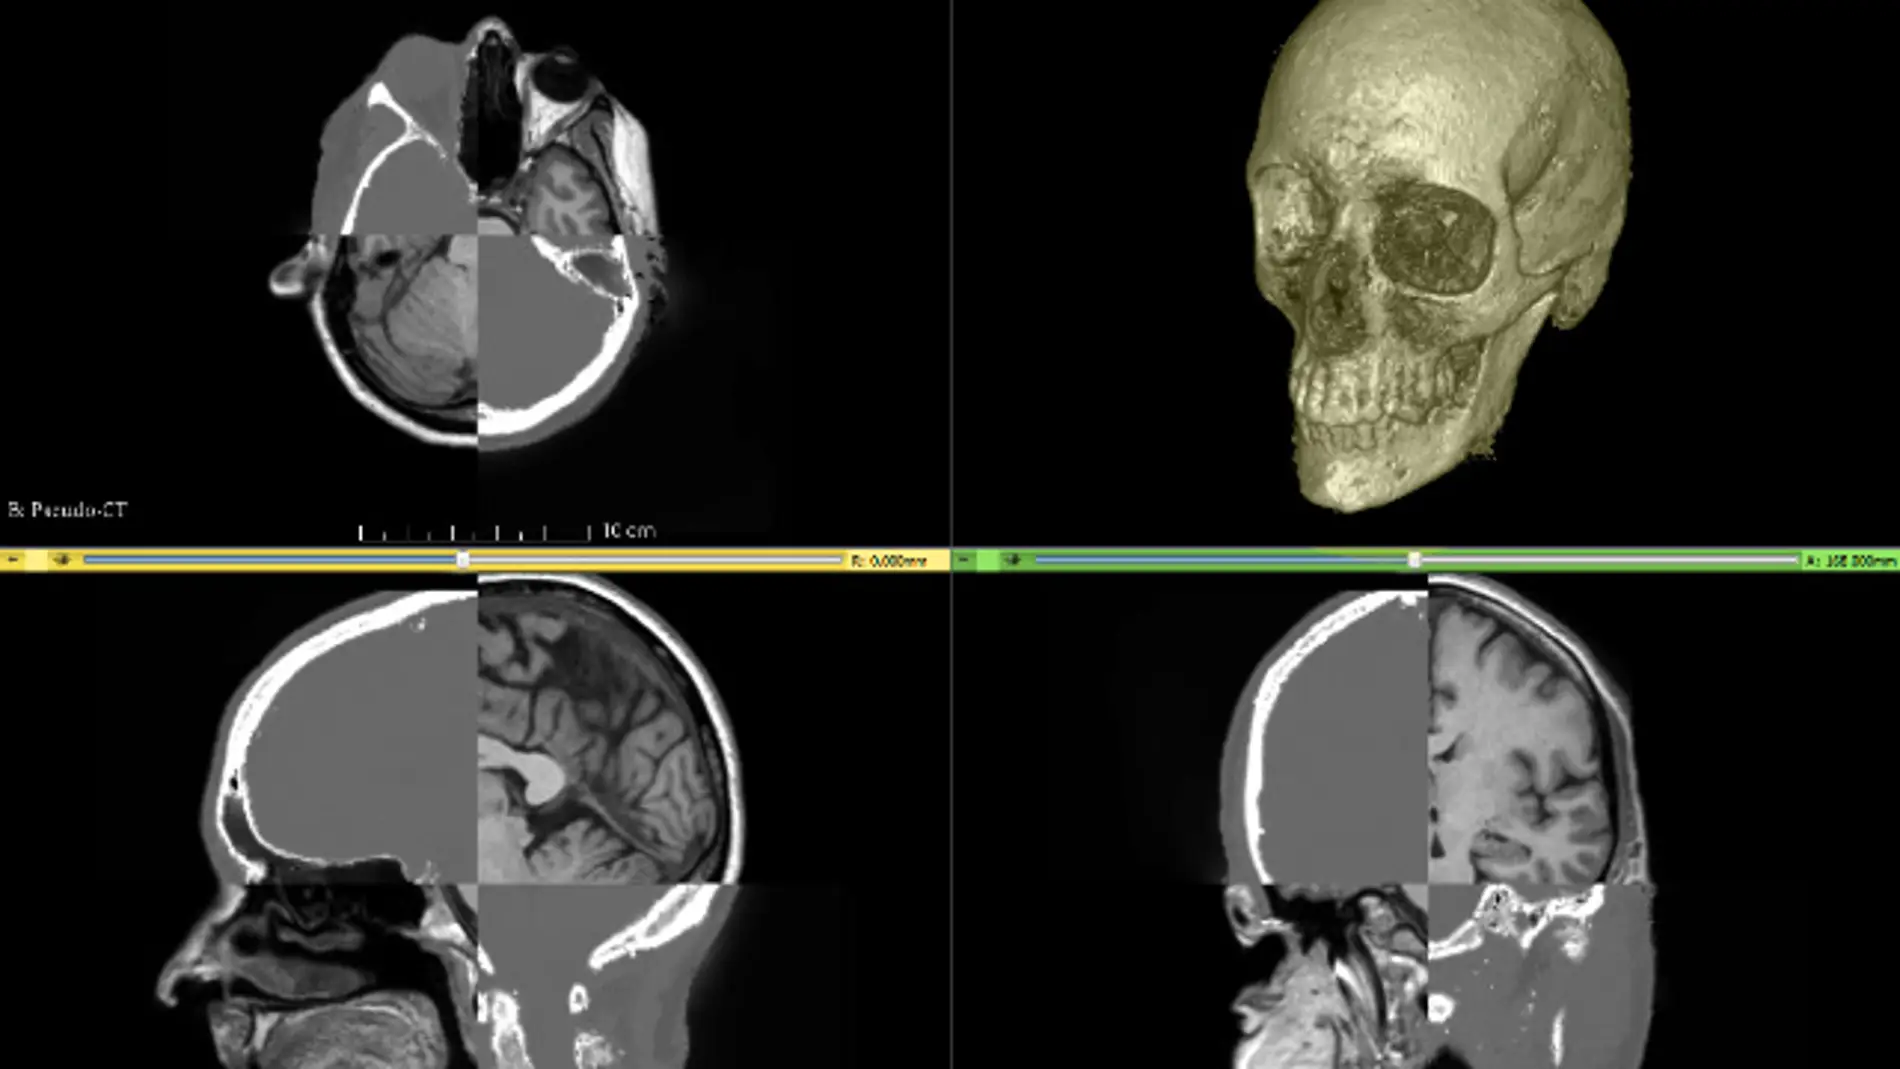

Investigadores de la Universidad Rey Juan Carlos han desarrollado un método para recrear el cráneo en imágenes obtenidas por resonancia magnética. Esto permite crear modelos específicos de cada paciente y mejorar la calidad de imagen, tanto de resonancia magnética como de tomografía por emisión de positrones (PET).

Ahora investigadores del Laboratorio de Análisis de Imagen Médica y Biometría de la red de laboratorios de Madri+d, gestionado por el Área de Tecnología Electrónica de la Universidad Rey Juan Carlos (URJC), proponen una técnica de tratamiento de imagen que estima la estructura y morfología del cráneo de un individuo, con la ayuda de una base de datos de imágenes de tomografía axial computarizada (TAC, que usa rayos X) y partiendo de las de resonancia magnética. El estudio se ha publicado en la revista Magnetic Resonance in Medicine.

“A partir de una imagen de resonancia magnética normal creamos un modelo anatómico completo de la cabeza de cada paciente”, explica Norberto Malpica, investigador de la URJC y coautor del estudio, quien añade que “en la imagen de resonancia magnética inicial separamos las distintas regiones: tejidos cerebrales, ojos, arterias, piel, agua, grasa y el cráneo para obtener toda la información necesaria”.

En la misma línea de trabajo, se ha mejorado la calidad de imagen en escáneres simultáneos PET-MR (tomografía por emisión de oositrones-resonancia magnética), donde es muy importante estimar la localización del cráneo, y así corregir la imagen de PET. En colaboración con el Hospital de Madrid Puerta del Sur y con investigadores del área de Computación de la URJC se ha desarrollado un método similar para esta aplicación. Este otro trabajo se ha publicado en el Journal of Nuclear Medicine.